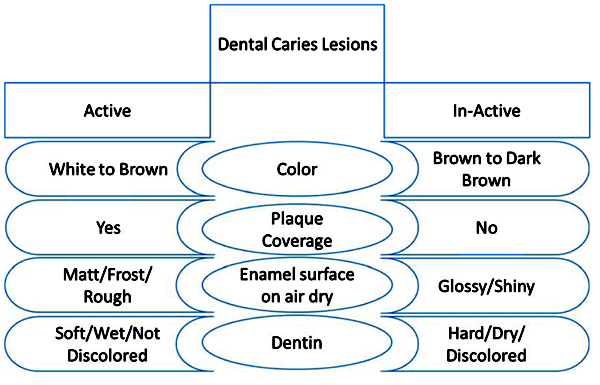

The accurate diagnosis of carious lesions is the key totheir proper management. In addition, current concepts for carious lesion detection have categorized the lesions as cavitated vs. non-cavitated lesionsand asactive vs. arrested lesions (Fig. 3). Fontana et al. in 2013 pointed out that the proper diagnostic process should consider the thresholds for non-surgical and surgical (i.e., restorative) interventions, risk assessment, and review of caries management interventions for caries disease management. Moreover, caries detection and management should be patient-centered, risk-based, and supported by the best available evidence, and they should consider the dentists’ clinical expertise and the patients’ needs and preferences [10].

Research has tended to focus on caries activity detection as a part of the modern caries management concept. This eventually aims to personalize each dental treatment plan according to the caries activity status. An active lesion has the possibilities to progress, regress, or be arrested, while an inactive (arrested) lesion is considered to have a lesser likelihood of transition [11]. More importantly,if the inactive non-cavitated carious lesions are not regularly monitored and managed, they threaten to progress into active lesions, resulting in dentine cavities, fillings, or extractions,depending on the severity of the lesion [12]. Caries lesion activity is usually assessed using visual-tactile criteria. Several studies determined the indicators that can be used to assess caries activity,including: the presence of plaque; the location of the lesion; the presence or lack of a shiny surface; and tactile characteristics (roughness) [13, 14]. Assessment of the surface topography and texture of lesions can help in the detection of caries activity. On gentle probing, an active lesion is matte and rough, whereas an inactive carious lesion is shiny and smooth [15]. It is important to establish a standard approach to distinguish between active and inactive carious lesions. However, there are some transitional stages between active and inactive lesions thatalso necessitate the use of a reliable and valid assessment tool.